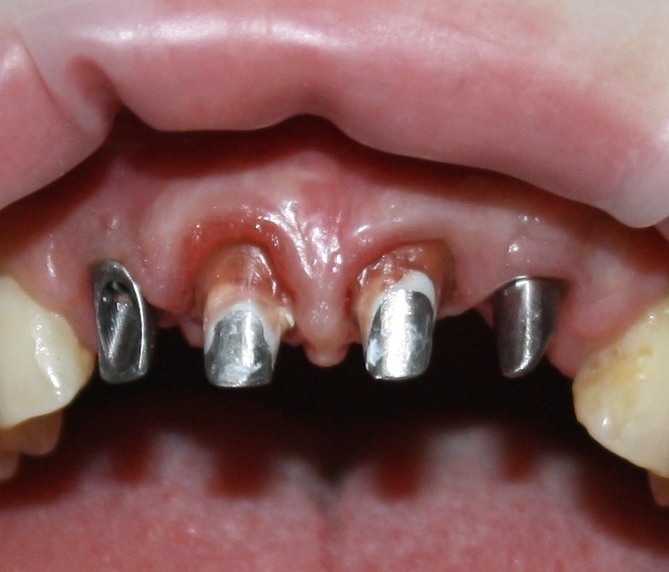

И вот, в жизни Марии наступил долгожданный день — окончательная фиксация керамических коронок на установленные имплантаты:

При этом, она ни дня не оставалась без зубов, была полностью социализирована и жила обычной жизнью. Спустя 5 месяцев после удаления, поставленную Марией клиническую задачу можно считать решёной. Но это с её точки зрения. С нашей же, всё самое интересное только начинается.